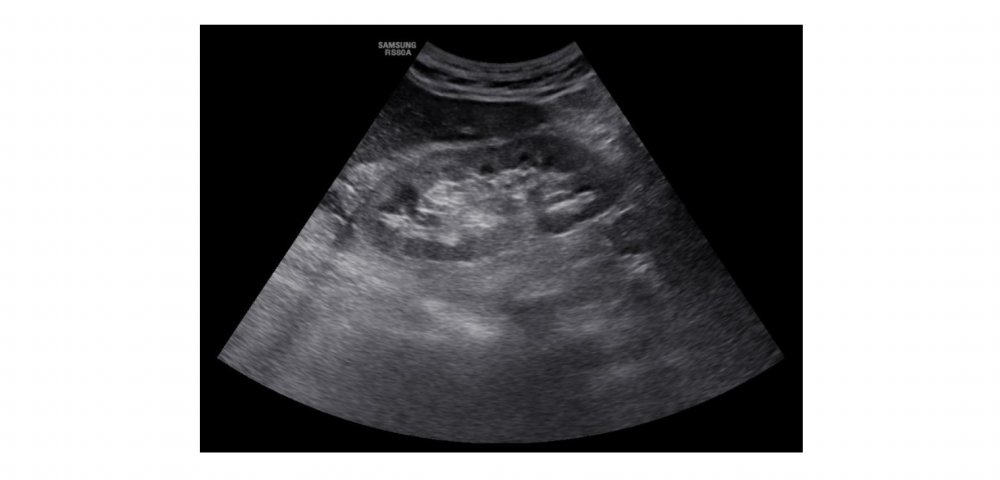

В съвременния начин на живот белтъците (протеините) са основни съставки в диетите на много хора, особено сред тези, които се стремят да изградят мускулна маса или да поддържат здравословно тегло. Но за хора с бъбречно увреждане или рискови фактори за развитие на бъбречни заболявания, високото количество белтъци в храната може да бъде нож с две остриета. Как повишеният прием на белтъци с храната оказва влияние на бъбреците? Бъбреците играят критична роля във филтрирането на отпадни продукти от кръвта. Белтъците, особено тези от животински произход, могат да увеличат натоварването върху бъбречната функция. При консумация на големи количества белтъци, бъбреците трябва да работят